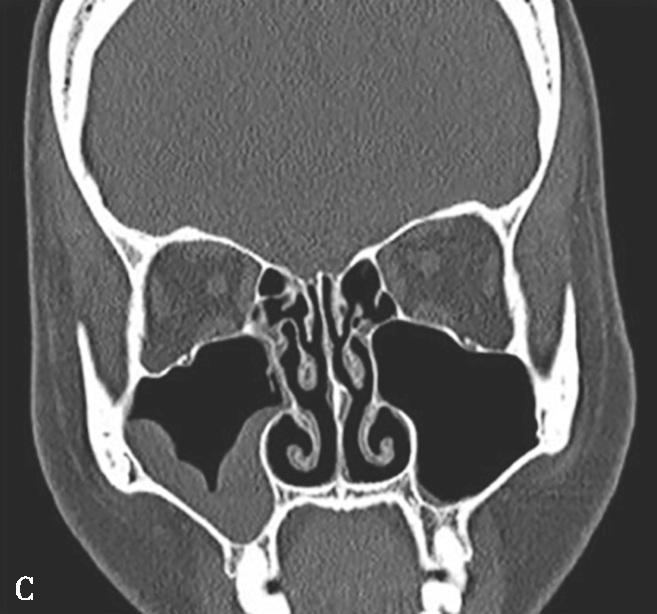

图1-3-22 变应性真菌性鼻窦炎

A、B.横断面、冠状面CT骨窗,示双侧上颌窦、筛窦腔膨胀,窦腔充填软组织密度影,病变内部可见片状磨玻璃样密度增高影,上颌窦壁骨质增生硬化;C.横断面CT软组织窗,示病变内部磨玻璃样密度影显示更清楚